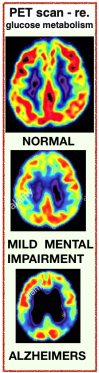

RESEARCH: For decades scientists studying the brain mainly focused on mental illness or physical injuries. Now advances in Neuroscience are beginning to identify complex mental processes & brain activity. EXPs:

▪︎ Scans of normal vs Alzheimer’s brains —->